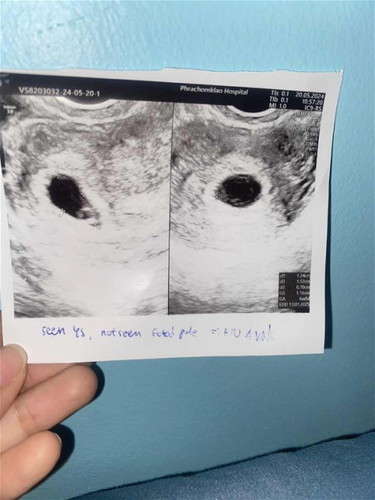

ขอสอบถามเรื่องการนับอายุครรภ์ค่ะ นับจากประจำเดือนหมดวันที่ 12 มีนาคม ไปหาหมอครั้งแรกวันที่ 20 พฤษภาคม หมอทำการอัลตาซาวครั้งที่ 1 เจอแต่ถุงการตั้งครรภ์ ไม่พบตัวอ่อน (จริงๆควรเจอตัวอ่อนแล้ว ) (มีรูป) หมอนัดอัลตาซาวครั้งที่ 2 วันที่ 17 มิถุนาคม เจอตัวน้องดิ้นแล้ว หัวใจเต้นแล้ว แต่ในใบซาว ขึ้น 9w5 เองค่ะ (มีรูปแนบ) คำถามคือเราควรนับตามใบซาวหรือนับจากประจำเดือนค่ะ #สาเหตุคืออะไรค่ะ เด็กโตช้า หรือไข่ตกช้าค่ะ ขอประสบการณ์แม่ๆค่ะ